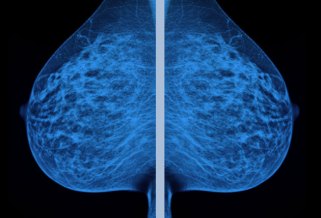

I thought I’d done everything right: breastfeeding my children, a careful diet, plenty of exercise. I wasn’t overweight and didn’t have a family history. I bought BPA-free bottles for my filtered water. But on a visit to the radiology department last spring, a pair of red brackets highlighted something worrisome on the ultrasound monitor.

Invasive lobular carcinoma—a malignant breast tumor. This spidery little beast measuring nearly three centimeters meant I had stage 2 cancer.

At 47, I was a decade and a half younger than the median age for breast cancer diagnosis in the United States. Was this just bad luck? Maybe, but the journalist in me was still curious to know: Why me? So I dug into the literature on risk factors to see where I might have fit in. It’s an impossible question to answer definitively for an individual, like trying to prove that a single weather event was caused by climate change. As one doctor told me, “You know who’s at risk for getting breast cancer? People with breasts!”

Still, most of the broad indicators didn’t seem to apply to me. The biggest one is age: The median diagnosis in the United States is at 62, and the highest breast cancer rates are in women older than 70. Another is taking hormone replacement therapy after menopause, but I’m premenopausal and haven’t taken it. Obesity raises risk, but I’ve never been overweight.

Researchers estimate that alcohol accounts for 15 percent of US breast cancer cases and deaths—about 35,000 and 6,600 a year, respectively. That’s about three times more than the number of breast cancer cases caused by a mutation of the BRCA genes, which prompted Angelina Jolie, who carries one of the abnormal genes, to have both her healthy breasts removed in 2013. The breast cancer risk from alcohol isn’t nearly as high as the lung cancer risk from smoking. But alcohol-related breast cancer kills more than twice as many American women as drunk drivers do. And alcohol is one of the few breast cancer risk factors women can control. Others, like starting menstrual periods before the age of 12 and entering menopause after 55, are baked in.

Overall, American women have about a 12 percent lifetime risk of getting breast cancer. Walter Willett, an epidemiology professor at the Harvard T.H. Chan School of Public Health who has conducted studies on alcohol and breast cancer, says a woman who consumes two to three drinks a day has a lifetime risk of about 15 percent—a 25 percent increase over teetotalers. By comparison, mammography reduces the death rate from breast cancer by about 25 percent. “Alcohol can undo all of that at about two drinks a day,” Willett says.

Human breast tissue doesn’t fully mature until a woman becomes pregnant. Before then, and particularly during puberty, breast cells proliferate rapidly, which may make them especially vulnerable to carcinogens. That’s one reason why never getting pregnant is itself a risk factor for breast cancer. Scientists have understood this for nearly 40 years, thanks to studies of women in Nagasaki exposed to radiation from the atomic bomb. Japanese women who’d been exposed before age 20 had the highest rates of breast cancer. Other studies suggest that the risk of premenopausal breast cancer goes up 34 percent for every daily drink consumed before the age of 30. And the longer women go between their first period and their first baby, the riskier drinking becomes.